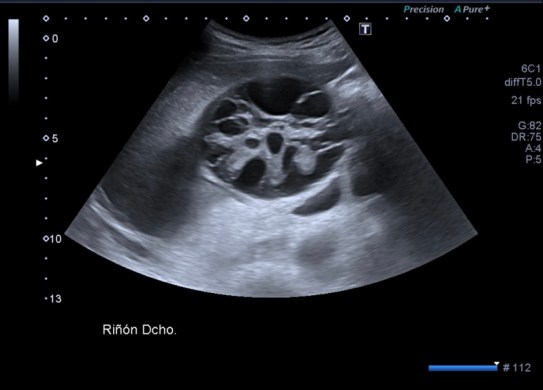

Lesión heterogénea, en el meso-riñón derecho, redonda, típica de quiste hidatídico.

Después de ver esta maravilla de imágenes, habiendo repasado el post 262 donde te explico las claves del quiste hidatídico, no tengo nada más que decir. Las imágenes hablan por si mismas. Perfectas, con una calidad increíble, el equipo increíble, bien ajustado, los parámetros adecuados, es un estudio perfecto, Sandra…yo lo sabía y te lo decía y estoy orgulloso, muy orgulloso de hacer esto que estoy haciendo ahora, en el día 2.

Un quiste hidatídico renal, maravilloso.